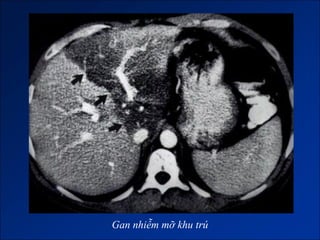

Hình ảnh trên CLVT

- Trước tiêm, tỷ trọng gan < tỷ trọng lách 10 HU.

- Các mạch máu trong gan hiện rõ.

- Sau tiêm, tỷ trọng gan < tỷ trọng lách 25HU or < tỷ trọng cơ.

- Gan nhiễm mỡ khu trú:

+ Thường ở HPT IV, cạnh dây chằng liềm.

+ Vùng nhiễm mỡ lan đến ngoại vi sát bao gan.

+ Không làm biến đổi bờ gan,

+ Không biến đổi cấu trúc mạch máu đi qua.

Gan nhiễm mỡ khu trú